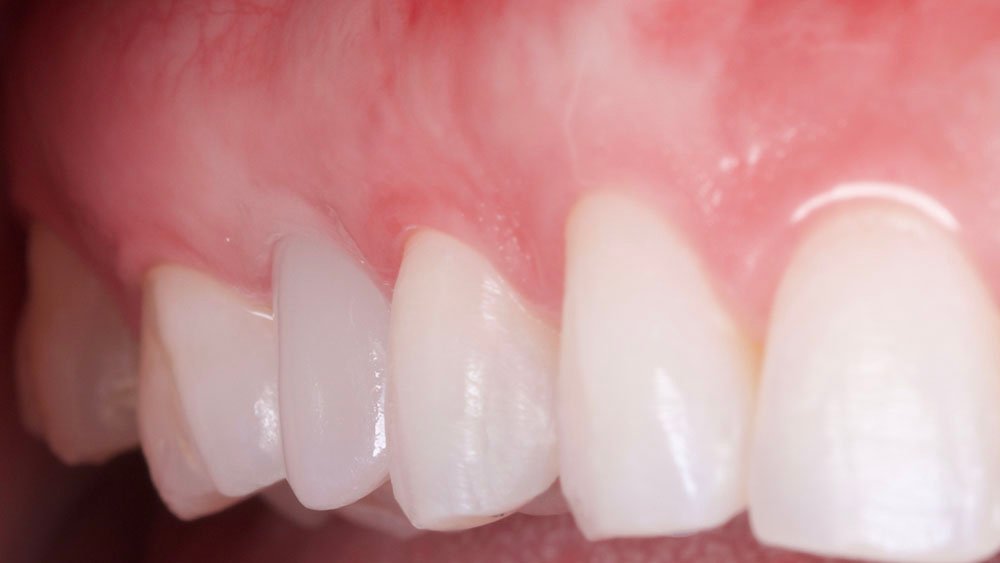

O procedimento selecionado para esse relato de caso promoveu resultados satisfatórios e melhorou a estética. No término do procedimento cirúrgico, a paciente foi orientada a tomar uma cápsula de Amoxicilina 500 mg (EMS – Germed Farmacêutica, São Paulo- Brasil) a cada 8 horas por sete dias; um comprimido de Nimesulida 100 mg (Eurofarma Laboratórios S/A, São Paulo-Brasil) a cada 12 horas por três dias; e um comprimido de Dipirona 500 mg (Sanofi Medley Farmacêutica Ltda., São Paulo-Brasil) a cada 6 horas. Além disso, foi indicado à paciente que evitasse alimentos pastosos e pegajosos, que preferisse alimentos frios ou gelados e utilizasse bolsa de gelo no local.

No acompanhamento mensal realizou-se proservação e radiografias periapicais da região para verificar a cicatrização dos tecidos e integridade do implante. Após o período de três meses, foi cimentada uma coroa definitiva de zircônia monolítica.